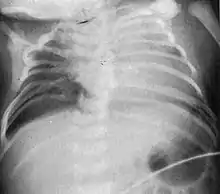

| Radiograph depicting typical skeletal features of Jarcho-Levin syndrome, subtype spondylothoracic dysplasia. Note fanlike configuration of the ribs, with extensive posterior fusion, along with multiple vertebral segmentation defects. | |

Spondylocostal dysostosis, also known as Jarcho-Levin syndrome (JLS), is a rare, heritable axial skeleton growth disorder. It is characterized by widespread and sometimes severe malformations of the vertebral column and ribs, shortened thorax, and moderate to severe scoliosis and kyphosis. Individuals with Jarcho-Levin typically appear to have a short trunk and neck, with arms appearing relatively long in comparison, and a slightly protuberant abdomen. Severely affected individuals may have life-threatening pulmonary complications due to deformities of the thorax. The syndrome was first described by Saul Jarcho and Paul M. Levin at Johns Hopkins University in 1938.[1]

Spondylothoracic dysplasia

Spondylothoracic dysplasia, or STD, has been repeatedly described as an autosomal recessively inherited condition that results in a characteristic fan-like configuration of the ribs with minimal intrinsic rib anomalies. Infants born with this condition typically died early in life due to recurrent respiratory infections and pneumonia due to their restricted thorax.[3][4][5] Recently, a report[6] has documented that actual mortality associated with STD is only about 50%, with many survivors leading healthy, independent lives.